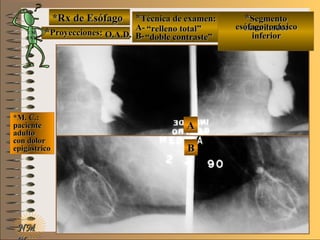

*Rx de Esófago*Rx de Esófago

**Proyecciones:Proyecciones:

**Técnica de examen:Técnica de examen:

A-A-

B-B-

**SegmentoSegmento

examinado:examinado:

*M. C.:*M. C.:

pacientepaciente

adultoadulto

con dolorcon dolor

epigástricoepigástrico

UNTUNT O.A.D.O.A.D.

““relleno total”relleno total”

““doble contraste”doble contraste”

esófago toráxicoesófago toráxico

inferiorinferior

A-A-El examen es normal o patológico?El examen es normal o patológico?

Examen patológico de esófago toráxico inferiorExamen patológico de esófago toráxico inferior

con técnica en A de relleno total y B de doble con-con técnica en A de relleno total y B de doble con-

traste en proyecciones O.A.D.traste en proyecciones O.A.D.

B-B-La patología es congénita o adquirida?La patología es congénita o adquirida?

Patología adquiridaPatología adquirida

C-C- Dicha patología es orgánica, funcional o mixta?Dicha patología es orgánica, funcional o mixta?

Patología adquirida orgánicaPatología adquirida orgánica

D-D-La misma es neoplásica o no neoplásica?La misma es neoplásica o no neoplásica?

Patología adquirida orgánica no neoplásicaPatología adquirida orgánica no neoplásica

E-E-Puede describir la o las imágenes patológicas?Puede describir la o las imágenes patológicas?

Se identifica en A una pequeña imagen de adiciónSe identifica en A una pequeña imagen de adición

y en By en B imagen deprimidaimagen deprimida UNTUNT (ver(ver

Terminolo-gíaTerminolo-gía UNTUNT )) que corresponden a ulceraque corresponden a ulcera

péptica en actividad (verpéptica en actividad (ver

formas de úlceras pépticasformas de úlceras pépticas UNTUNT))**Opción avanzada para volver a ver las imágenes con reparosOpción avanzada para volver a ver las imágenes con reparosNMNM